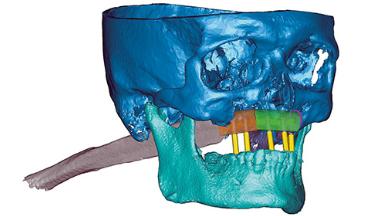

This case outlines a complex reconstruction involving use of a preconstructed fibula graft pre-installed with implants. It demonstrates the benefits of backwards planning from the desired occlusion using digital planning and 3D printing. A 43-year-old male patient was referred to the department of Oral and Maxillofacial Surgery, University Medical Center Groningen, Netherlands for secondary reconstruction of the maxilla. Twelve years previously, a hemimaxillectomy had been performed elsewhere because of a maxillary osteosarcoma. The resulting defect had been reconstructed using a deep circumflex iliac-artery flap and radial forearm flap.